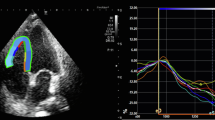

Speckle-tracking echocardiographic analysis

Biventricular strain measurements were acquired according to recommendations by ASE and European Association of Cardiovascular Imaging and recorded as absolute values for simpler interpretation [24]. All images were analyzed using TOMTEC-ARENA TTA2 software and measurements were obtained by a single author with verification by cardiology faculty. LV GLS was measured using the apical 4-, apical 2-, and apical 3-chamber views. RV GLS was measured using the apical 4-chamber RV-focused view. After tracing the LV and RV endocardial borders, manual correction of the automatically generated region of interest was performed to achieve optimal tracking and inclusion of the myocardium, if necessary. LV GLS was automatically computed by the software as the average segmental strain components in an 18-segment model. RV GLS was automatically computed by the software as average segmental strain components for the basal, mid, and apical segments of the RV free wall and septum.